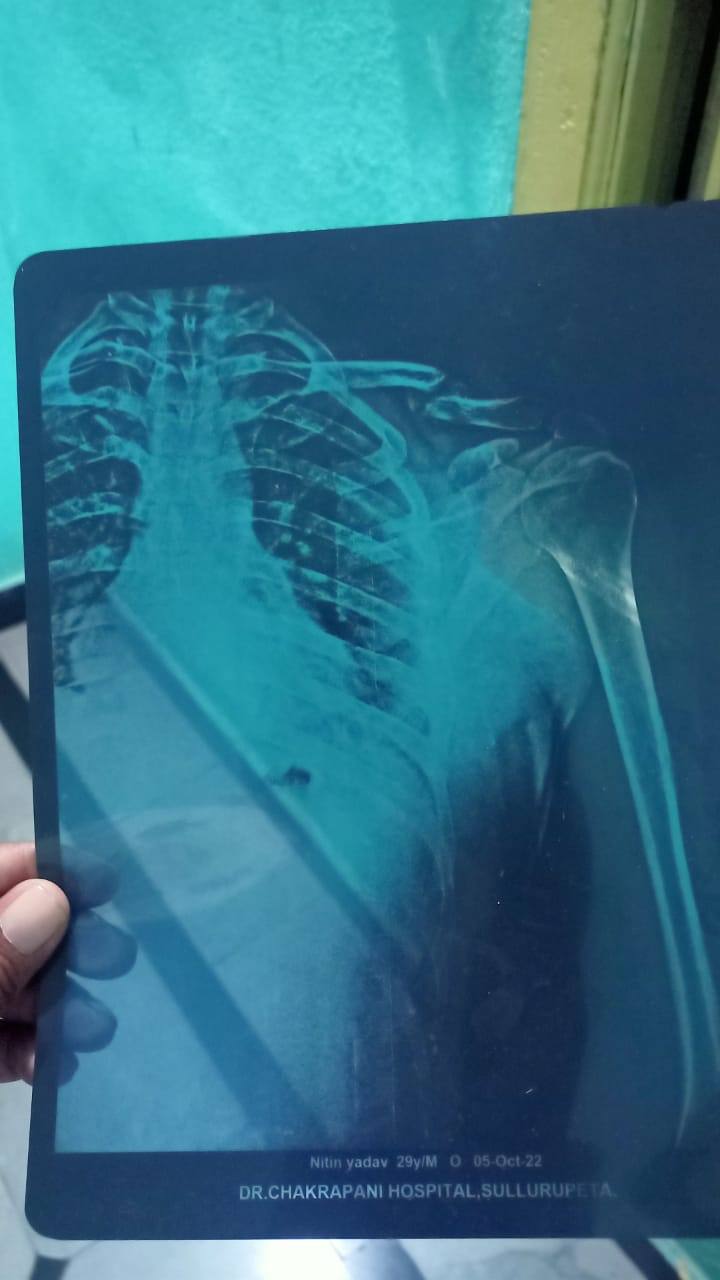

Sir Meri clavicle bone accident m tuut gyi h ...15 January 2022 ko accident hua tha..Please aap mujha kuch suggestion de ki y kaise thik hogi...